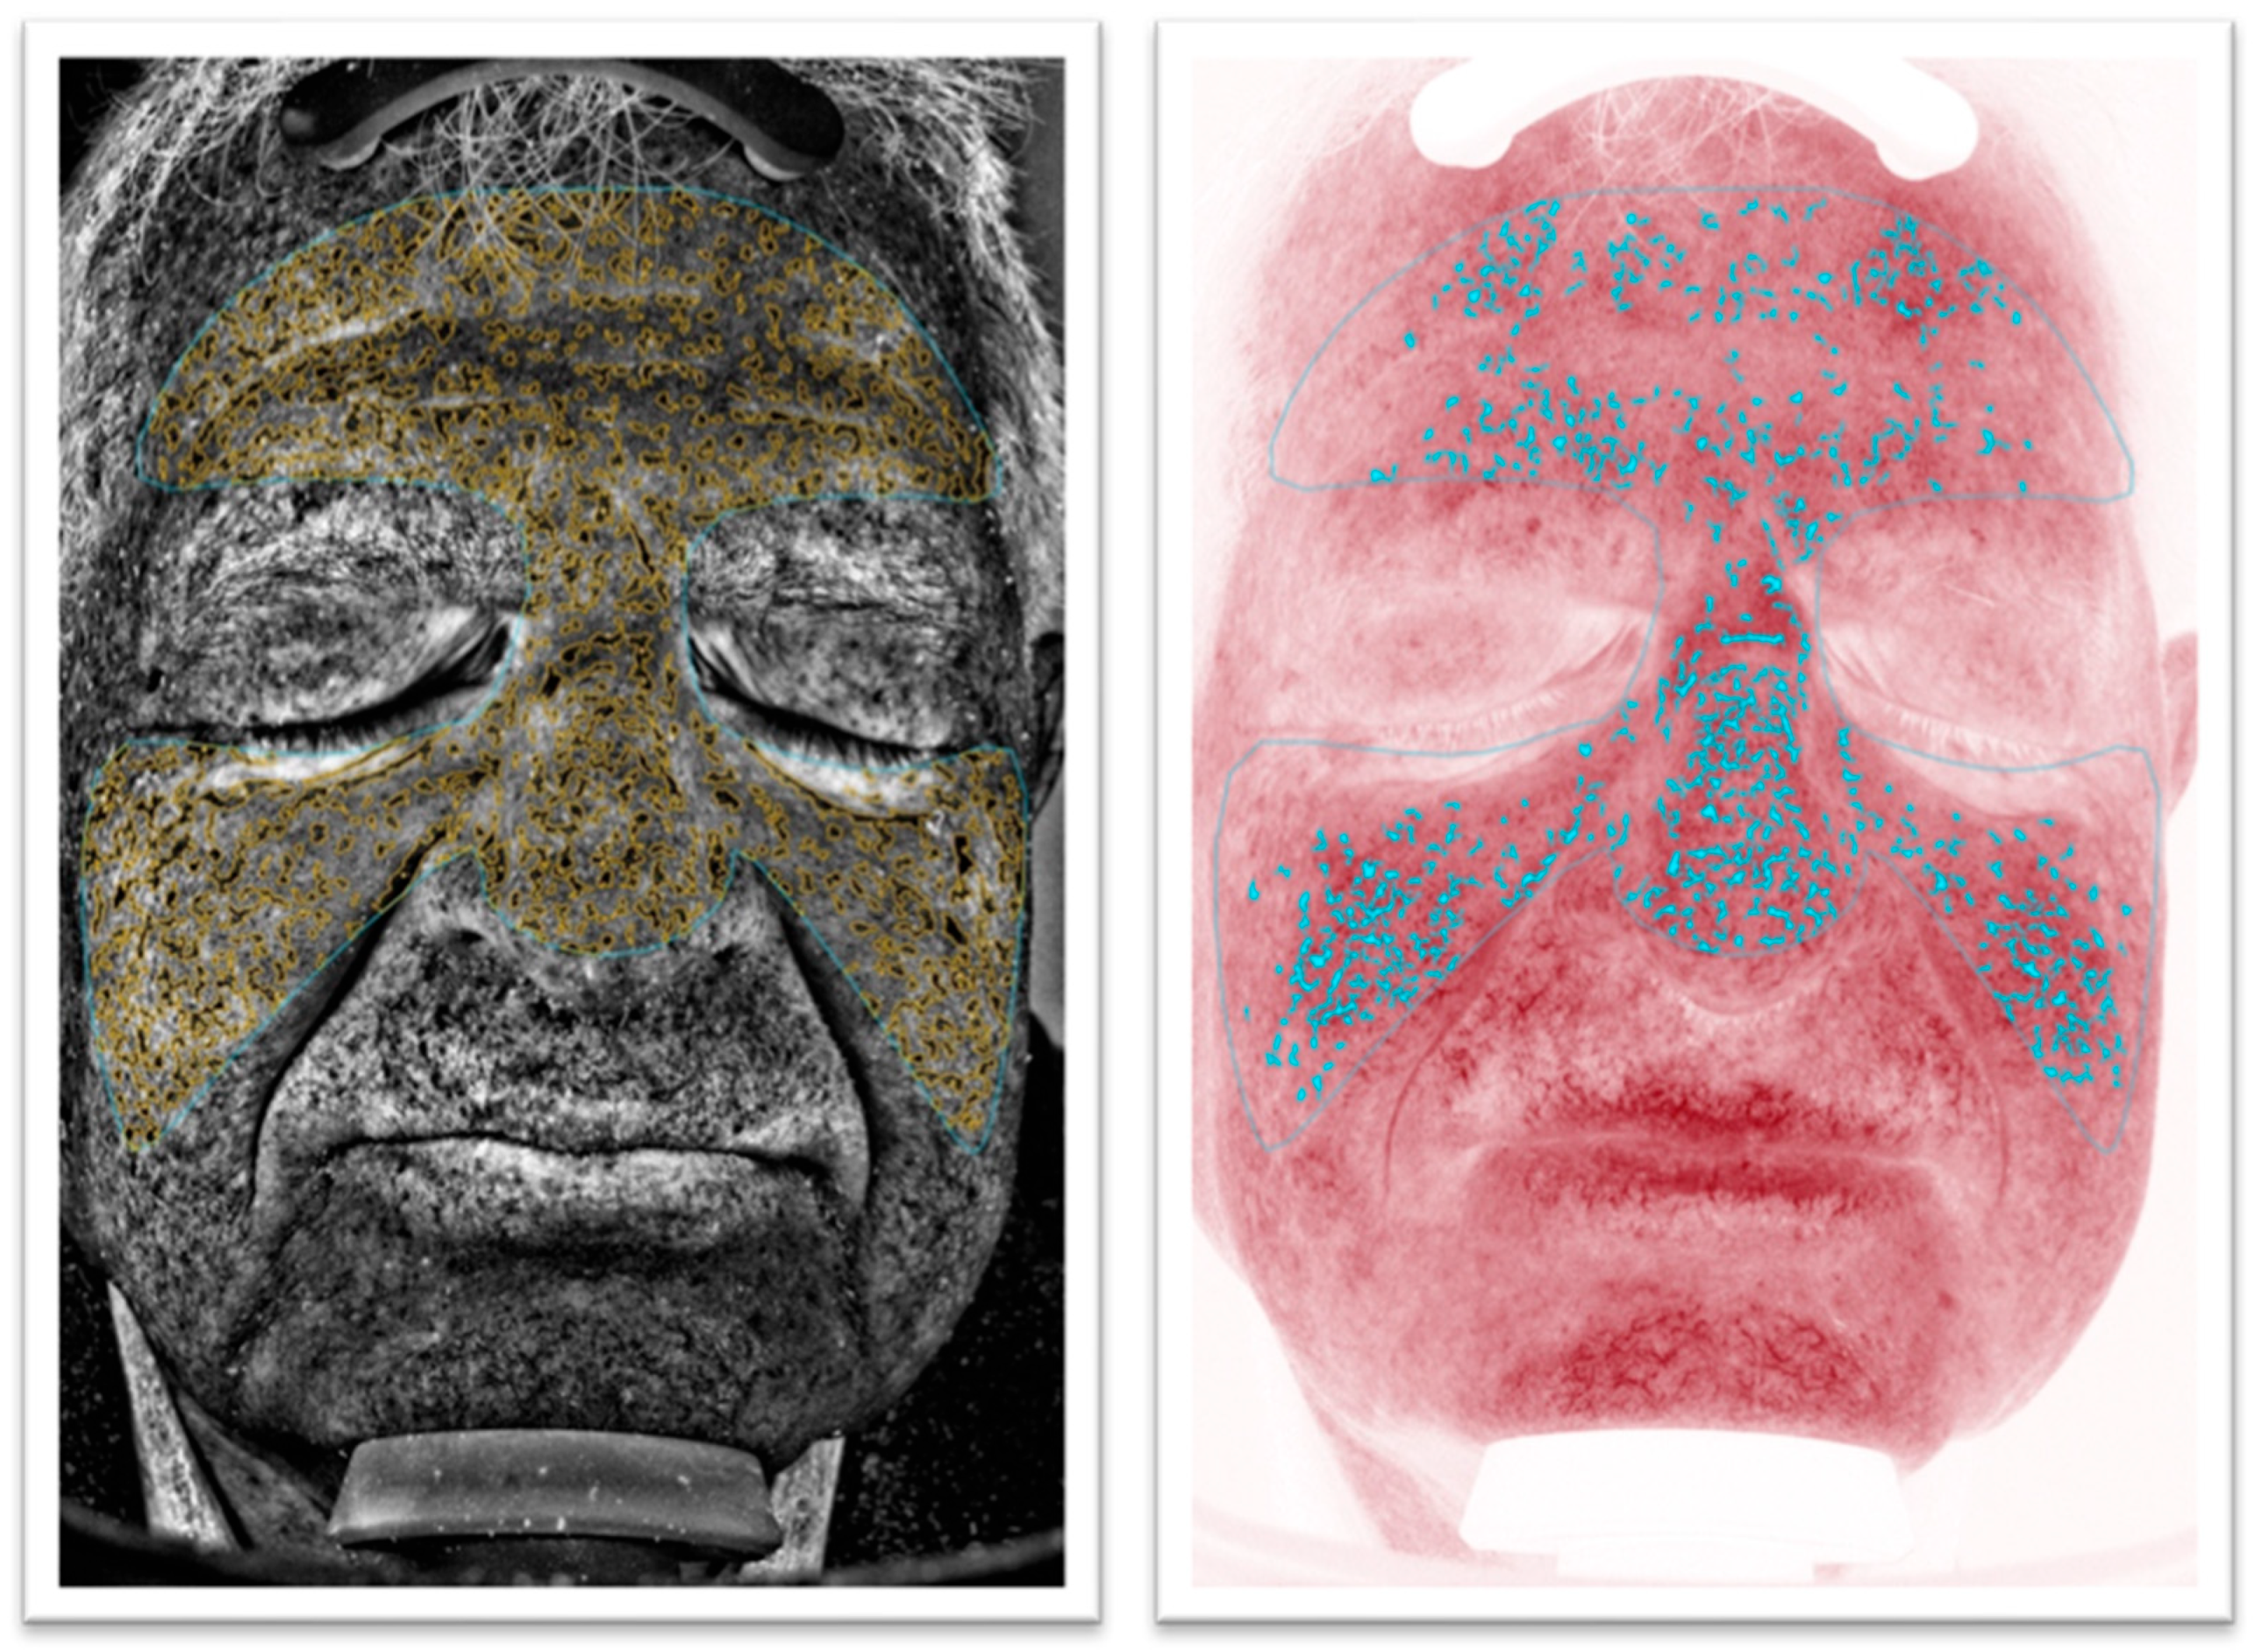

2.2. Imaging Check-Up Procedure

2.3. Study Aims and Protocol